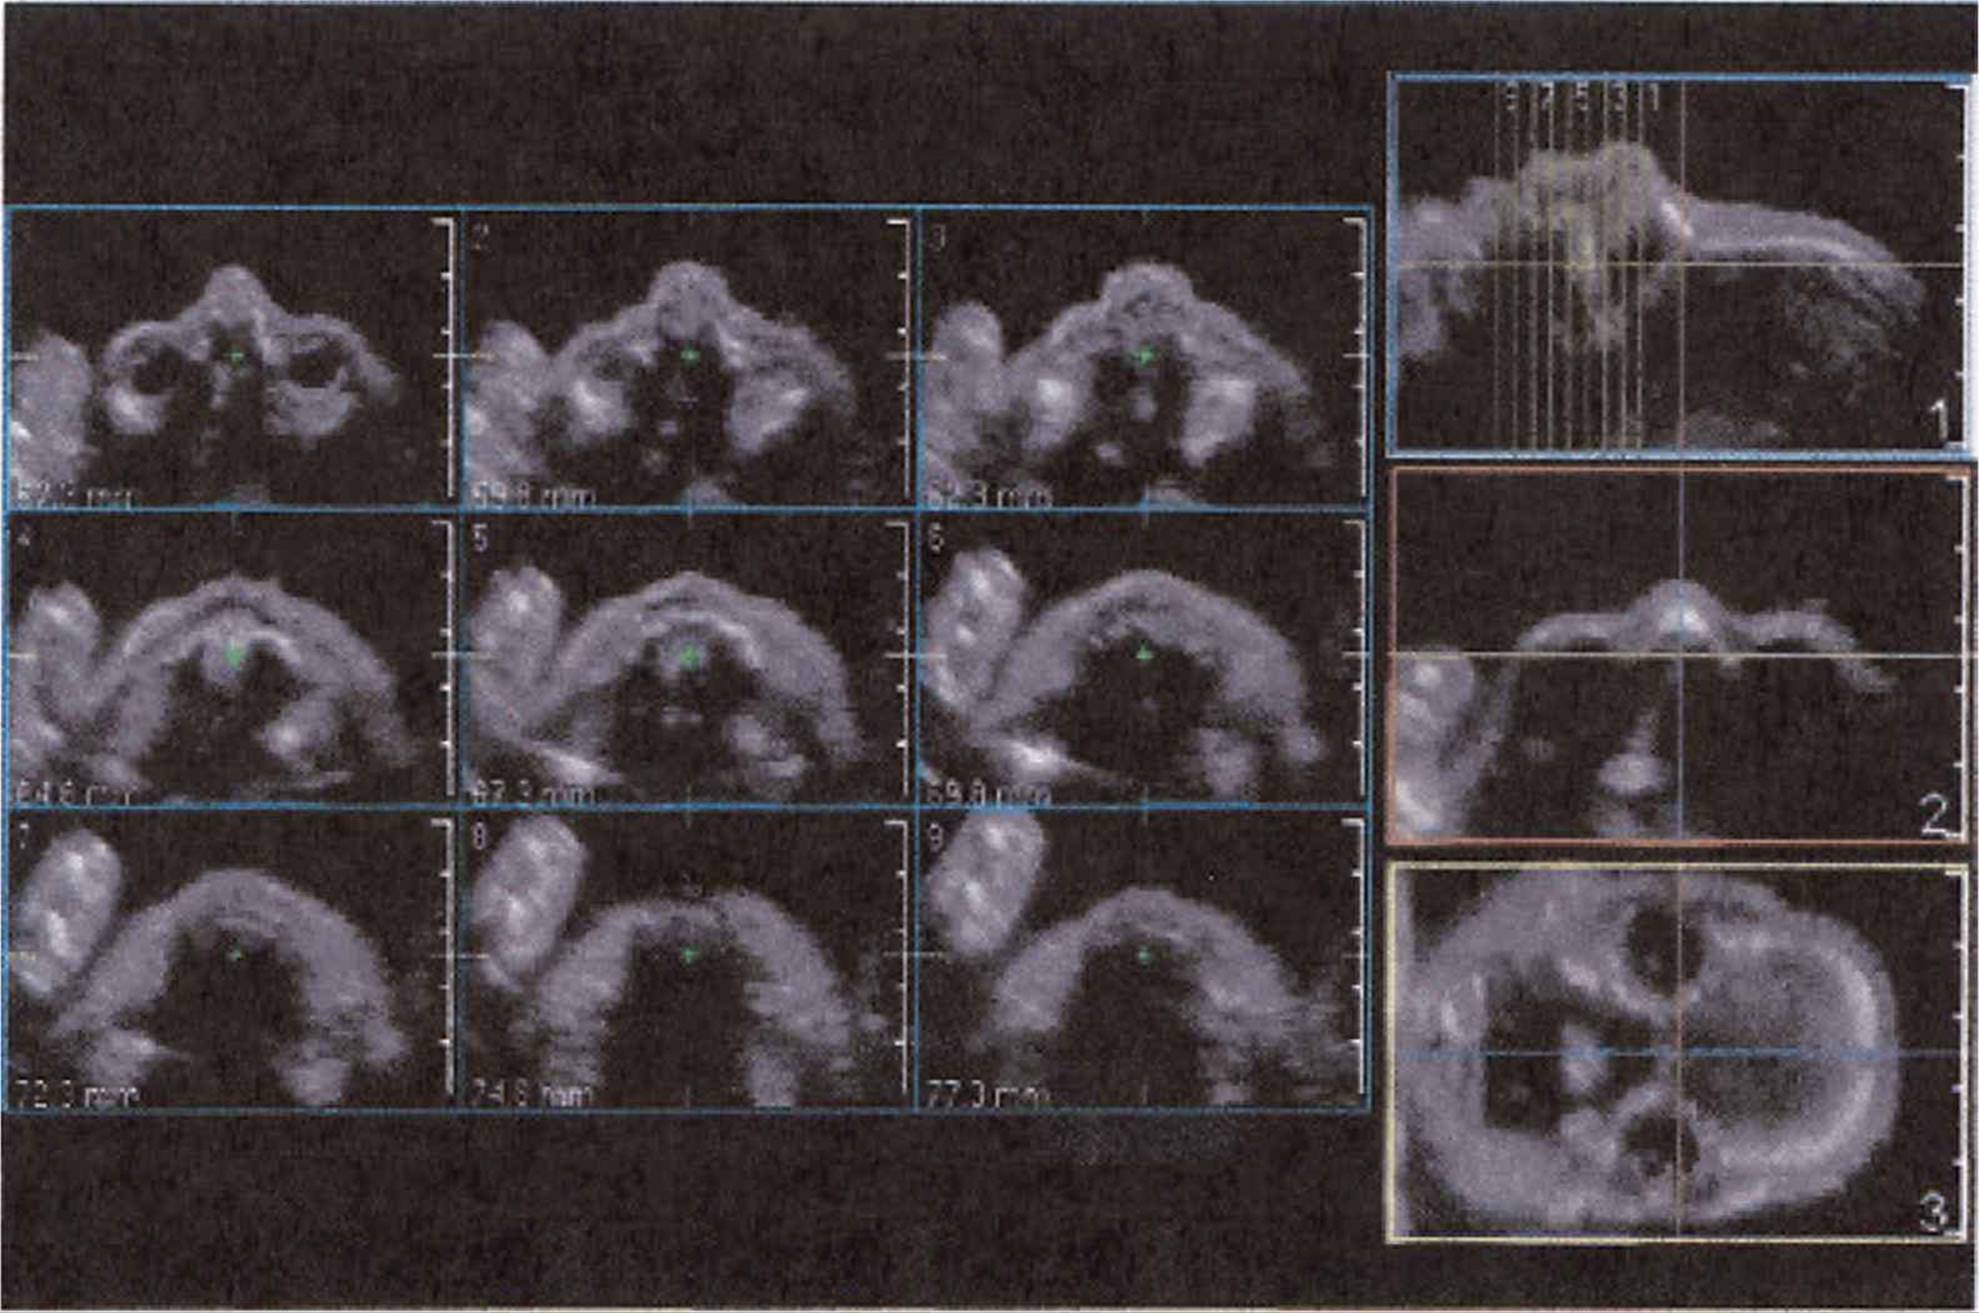

This layout of multiplanar reconstructed images can be varied to emphasize the volumetric images as the largest one displayed. Three-dimensional images can be manipulated to emphasize the surface (surface rendering) or the entire volume (volume rendering). The ability to visualize the structure from a selectable scan plane is particularly helpful when such planes cannot be readably obtainable from a 2D image. This is particularly true in the evaluation of the fetal heart when obtaining an optimal image of the outflow tracts, this may not be possible on 2D acquisition but quite possible with 3D. Another new feature is the ability to display multiple tomographic images (Philips’ iSlice) obtained in selectable intervals and slice thicknesses.

FIGURE 8–10. iSlice 3D showing normal fetal palate. (Courtesy of Philips Healthcare.)

FIGURE 8–11. iSlice 3D showing normal fetal palate and mandible. (Courtesy of Philips Healthcare.)